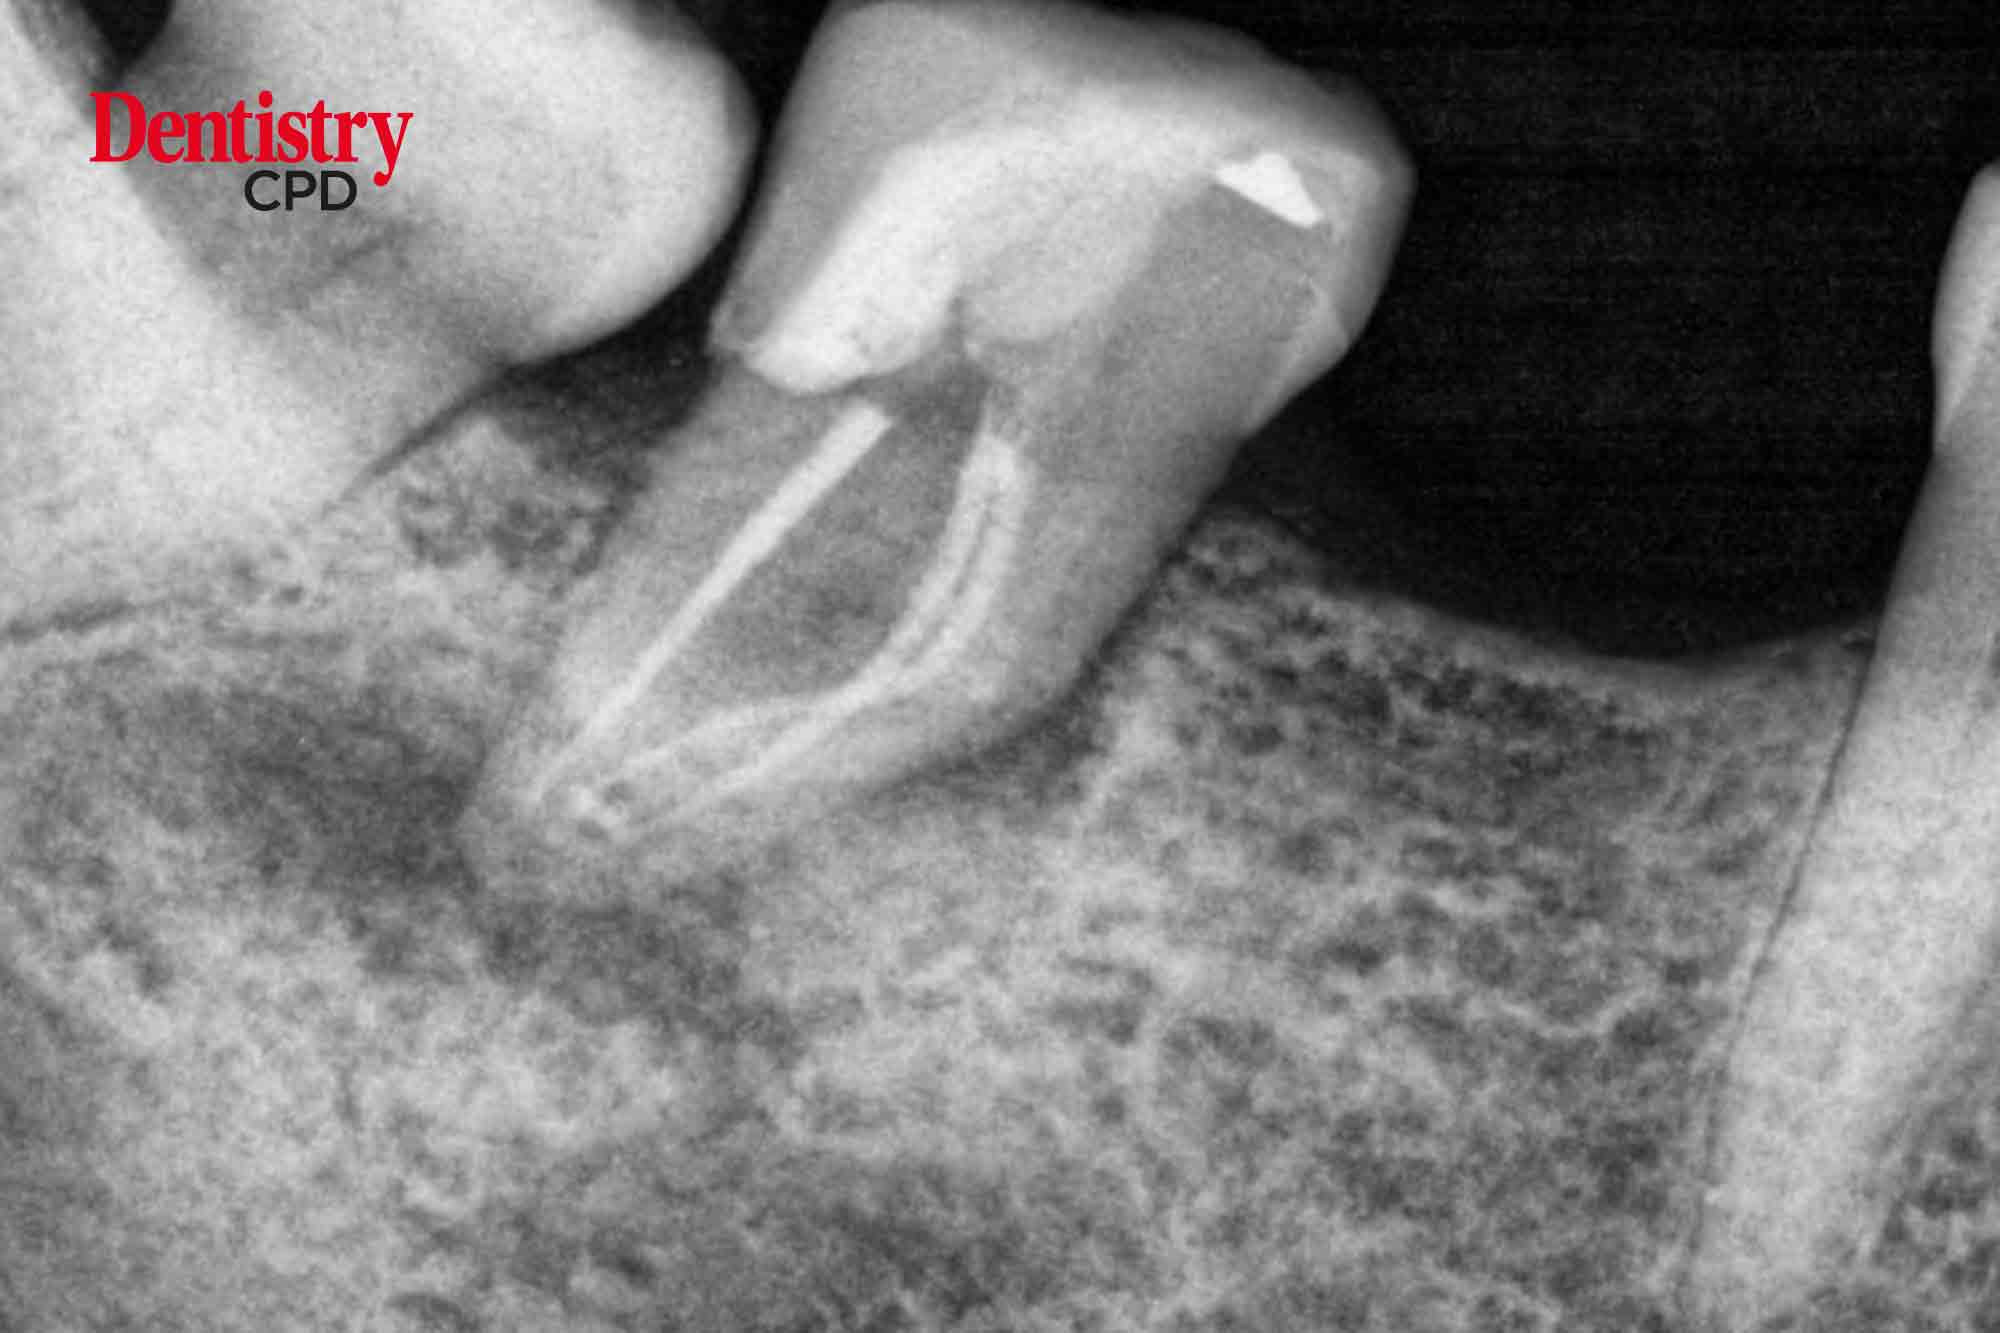

Richard Mounce and Brett Gilbert provide the clinical, foundational and sequential stages of an orthograde endodontic procedure

To recount the clinical, foundational and sequential stages of an orthograde endodontic procedure